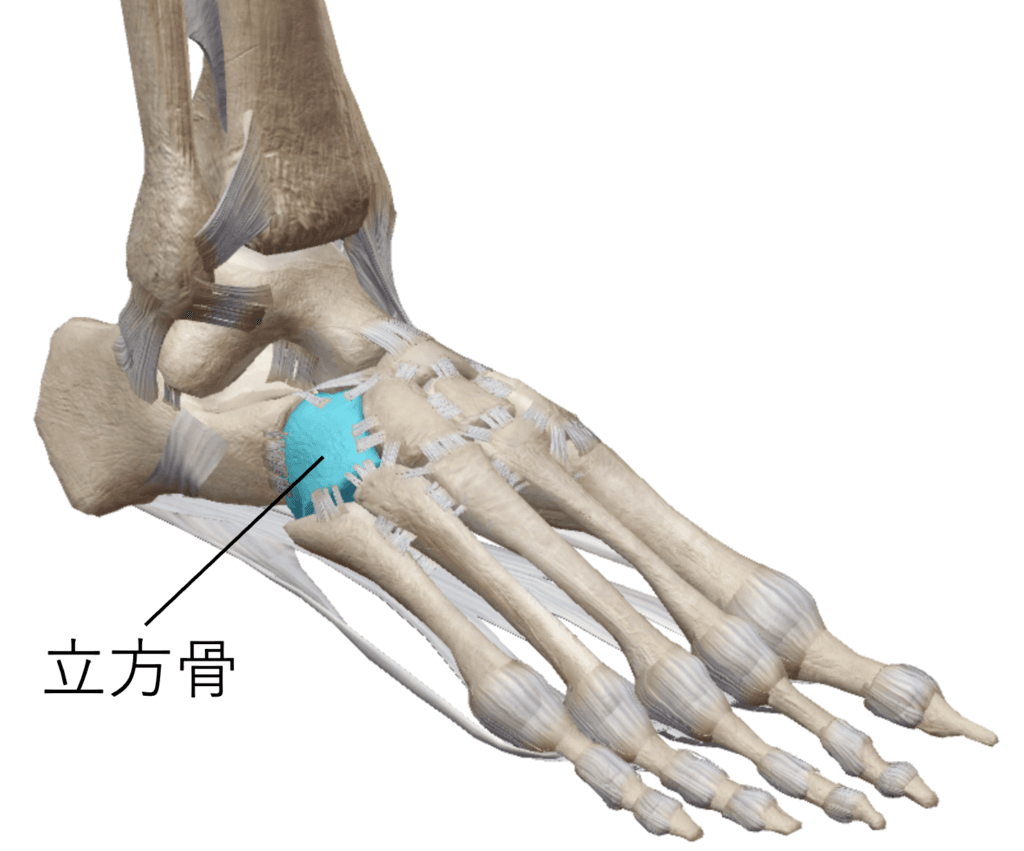

今年の9月中旬に左足を捻ってしまい、整形外科に受診をしてレントゲンを撮ったところ左足の「立方骨骨折」と診断を受けられました。